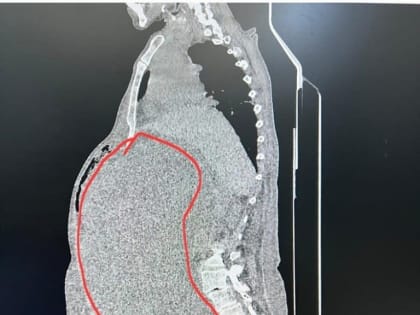

Врачи онкодиспансера Ставрополя избавили пациентку от 17-килограммовой опухоли

Пациентка К. 66 лет поступила в отделение онкогинекологии с жалобами с февраля на увеличение живота в объеме, выраженную слабость и отеки нижних конечностей.